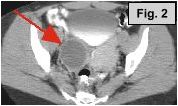

Fig. 1a-c: MRI of the L-spine (sagittal T2 weighted, coronal scout, and coronal MR Myelogram, respectively) demonstrates an incidental 4-5 cm cystic-appearing mass in the right pelvis on limited views of the pelvis. Fig. 2: a helical CT image of the pelvis, revealing a 4x5 cm low-density mass in the right hemipelvis to the right of the uterus. Fig. 3: Pelvic ultrasound shows a moderately enlarged right adnexa measuring 5 cm with low-level echoes.

IMAGING FINDINGS:  Fig. 1a-c show MRI images of the L-spine (sagittal T2 weighted, coronal scout, and coronal MR Myelogram, respectively).  They demonstrate mild scattered disc bulges and an incidental 4-5 cm cystic-appearing mass in the right pelvis on limited views of the pelvis. Incidentally, the MR Myelogram (Fig. 1c) also nicely shows the thecal sac and renal collecting systems.  Fig. 2 shows a helical CT image of the pelvis, revealing a 4x5 cm low-density mass in the right hemipelvis to the right of the uterus with CT density of about 20 Hounsfield units on pre- and post-contrast images.  A repeat transabdominal and endovaginal pelvic ultrasound with Doppler performed at AIC (Fig. 3) showed a moderately enlarged right adnexa measuring 5 cm with low-level echoes.

DIFFERENTIAL DIAGNOSIS:  Based on the CT, MRI, and ultrasound findings, a complex cystic or solid adnexal mass was suspected.  Low density on CT and low-level echoes on ultrasound are fairly typical of an endometrioma, which was suggested as a possible diagnosis, although a tumor such as a cystadenoma or cystic teratoma could not be excluded.